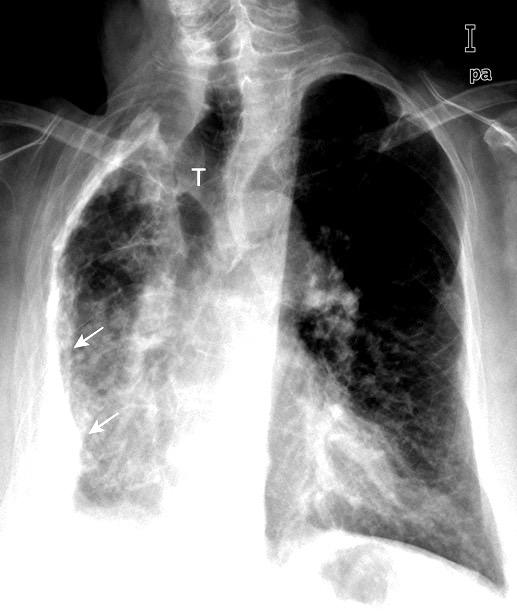

Triada de Garland

Ganglios paratraqueales derechos e hiliares bilaterales

95% de pacientes tienen ganglios hiliares bilaterales aislados o con afectación mediastínica (espec. paratraqueal derecho).

Criado E et al. Pulmonary sarcoidosis: typical and atypical manifestations at high-resolution CT with pathologic correlation. Radiographics. 2010